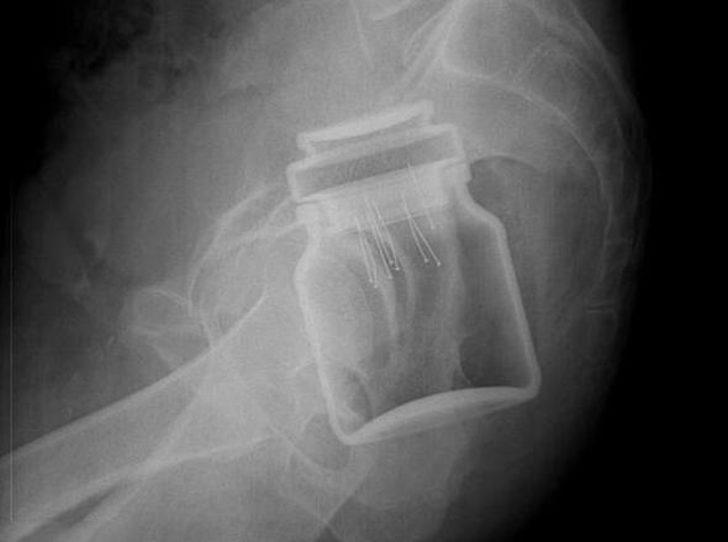

Açıklanan raporlar arasında acil durum şikayetiyle ilgili olan görenleri hayrete düşürdü. Oldukça ilginç bulunan bu raporda röntgen cihazlarda çekilen filmler yer aldı. Bakın o filmlerde nasıl görüntüler vardı?

Röntgen filmlerinden öyle şeyler çıktı ki...